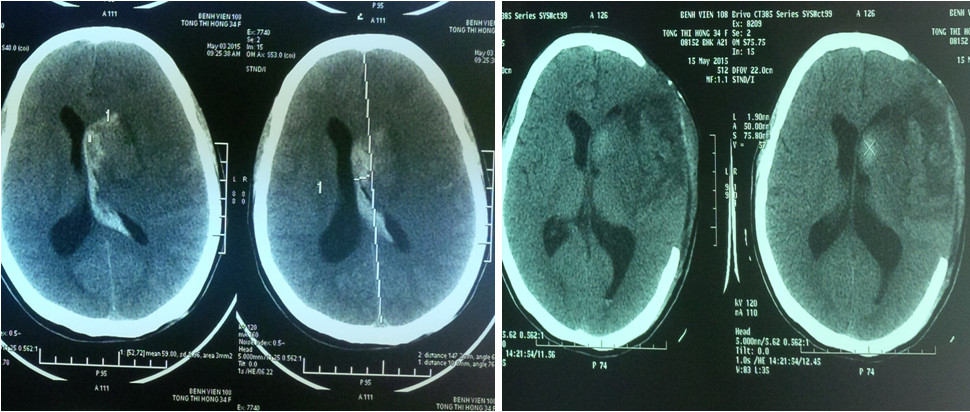

- Nhồi máu diện rộng khu vực cấp máu động mạch não giữa (thể tích ổ nhồi máu >145ml hoặc hơn 50% khu vực cấp máu động mạch não giữa.

- Có đè đẩy đường giữa trên CT.

Hubet5555 chuẩn mã hóa SSL quốc tế khi có chỉ định Hubet8888 lì xì hội viên mới mở sọ giảm áp, thân nhân sẽ được tư vấn đầy đủ về những rủi ro cũng như lợi ích mang lại. Khi có sự đồng ý của gia đình, Hubet8888 lì xì hội viên mới viên sẽ mổ lấy bỏ đi một phần xương sọ đủ lớn để tổ chức não bị phù nề có không gian thoát ra ngoài, giảm áp lực nội sọ. Qua đó, làm tăng áp lực tưới máu não, làm giảm tổn thương do tăng áp lực nội sọ. Phần xương sọ lấy bỏ sẽ được bảo quản tại ngân hàng mô, viện Bỏng quốc gia. Sau 1-3 tháng, nếu tình trạng Tại game HUBET cho phép sẽ Hubet8888 lì xì hội viên mới đặt lại bản xương sọ.